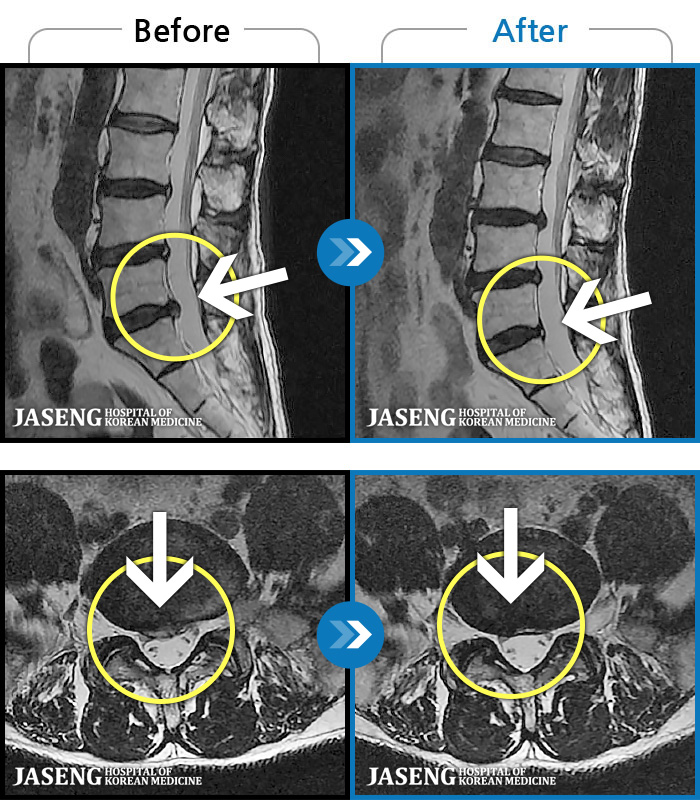

허리디스크

도움받은 사례

일산 · 김진수 원장

처음 내원 시 좌측 엉덩이가 많이 아프고, 좌측 다리로 저림이 심하며 특히 좌위시 하지 방사통이 심하여 1분도 좌위가 어려워 식사도 서서 하는 등 정상적인 활동이 힘든 상태였습니다.

촬영시기

2021.11.12 ~ 2024.07.23

2024.11.08

조회수 587